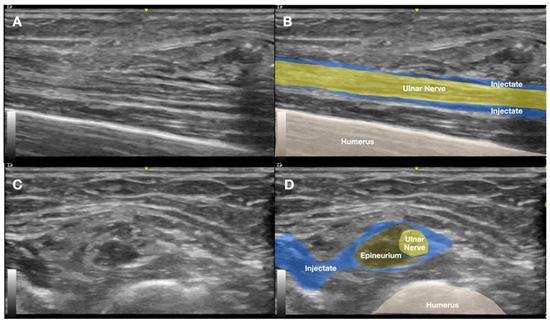

2.1. Prior Imaging Included Radiography (Figure 3), Which Confirmed the Implant’s Location, and Ultrasound (Figure 4), Which Demonstrated Its Proximity to the Ulnar Nerve